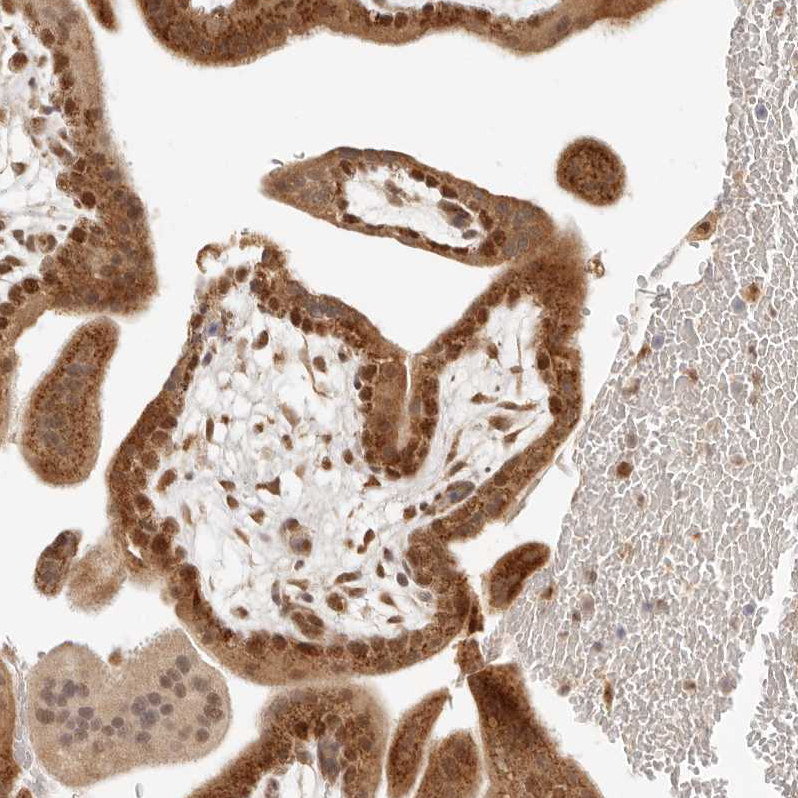

Immunohistochemical staining of human testis shows strong cytoplasmic positivity in Leydig cells, as well as moderate cytoplasmic and nuclear positivity in cells in seminiferous ducts.